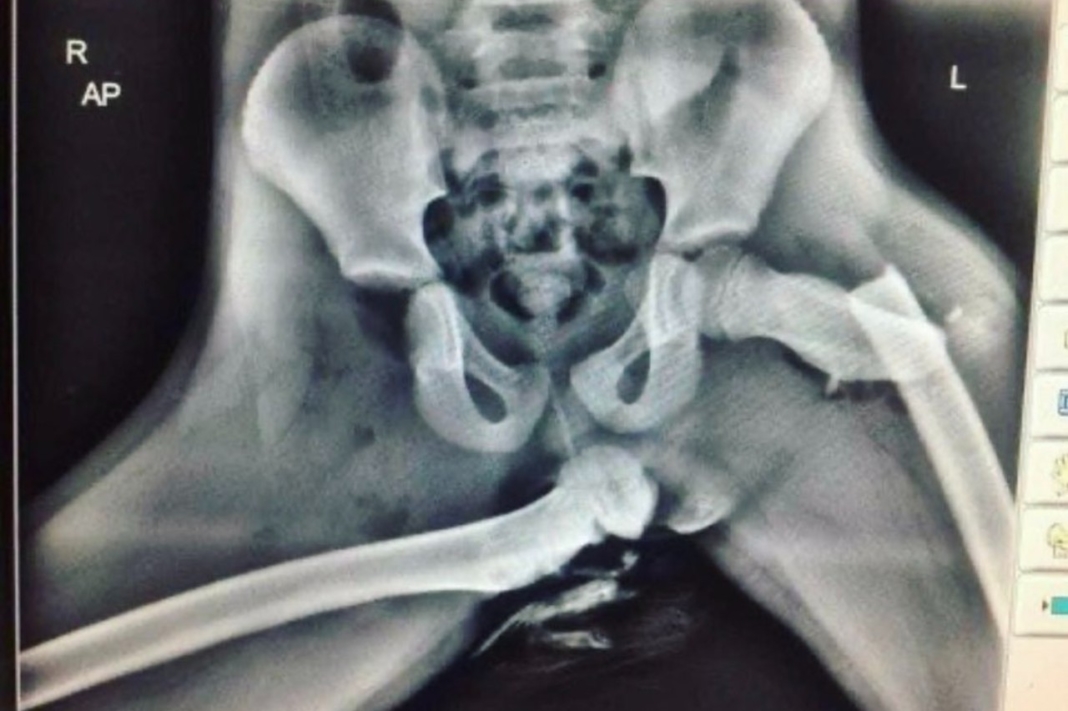

Quizá en la teoría cueste visualizar lo que ocurre, pero la imagen que ilustra estas líneas y que compartió @VdeVeroReal en Twitter muestra claramente el destrozo que puede derivar de un accidente yendo en esta posición, con un fémur partido prácticamente a la altura de su cabeza y otro directamente sacada de su lugar:

Una imagen vale más que mil palabras.

Los peligros de viajar con los pies en el salpicadero.